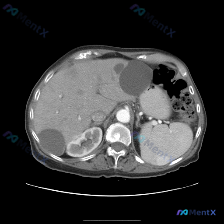

今天整理了一份上腹部增强CT的病例,关于脾脏结节的读片和鉴别思路,分享一下: 先看完整影像表现 这是一张上腹部增强CT横断面(软组织窗),对比剂显影良好,主要观察到两个核心异常: 1. 肝脏:肝左外叶、右后叶各见一个类圆形低密度灶,边界清、无强化,符合典型肝囊肿表现; 2. 脾脏:脾实质内见一个类圆...